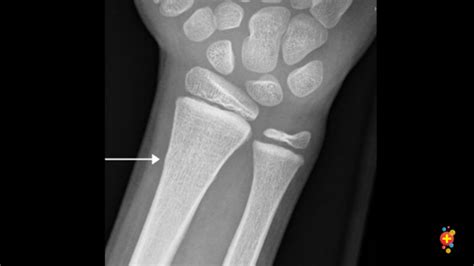

A buckle fracture, also known as a torus fracture, is a type of fracture that occurs in the wrist, typically in children. It is a common injury that occurs when a child falls onto an outstretched hand, causing the bone to bend and partially break. The fracture gets its name from the fact that the bone "buckles" or bends, rather than completely breaking. Buckle fractures are often seen in the distal radius, which is the bone in the forearm that connects to the wrist.

- Buckle fractures are often seen in the distal radius, which is the bone in the forearm that connects to the wrist.

The symptoms of a buckle fracture can vary depending on the severity of the injury. Common symptoms include pain, swelling, and limited mobility in the affected wrist. In some cases, the fracture may also cause numbness or tingling in the hand or fingers. To diagnose a buckle fracture, a doctor will typically perform a physical examination and take a medical history. They may also order imaging tests, such as X-rays or a CT scan, to confirm the diagnosis and assess the severity of the fracture.